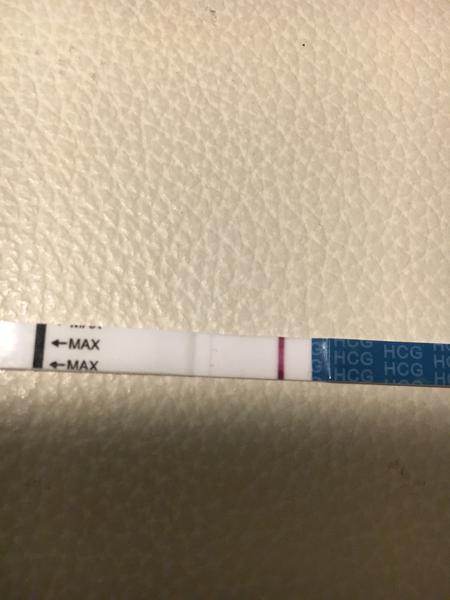

Těhotenský test. Dávám fotku. Co myslíte?

dnes jsem si dělala testík...

Udělal jsem radši ještě jeden - jmenuje se ForYou... Tam se objevil slabý duch, ale až tak za 3minuty! Šla jsem ven se psi a když jsem se vrátila, tak duch byl silnější...no ale to bylo skoro po půl hodině!

Tak nevim ... ☹ Dávám fotku, skuste posoudit...

@flylight tak já ho zkoušela taky, mám ho i tady v zásobě. Některé testy mají menší barvivo, takže můžou ukázat čárku později, než jiné. S tímto testem nemám zkušenost, že by dělal falešné čárky. A když se objevila, tak je to jasné 🙂 Někomu se hold i ty čárky ukáží po vynechání MS, taky se říká, že to je nejjistější pro testování.

Já tam čárku vidím 🙂 v té době jsem měla taky jen nepatrnou druhou čárku 🙂